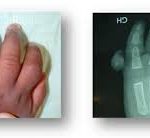

RADIOLOGICAL ASSESSMENT:

X-rays of the wrist in front and in profile, and specific scaphoid incidences (Schneck’s incidence).

On X-rays, it is sometimes difficult for a non-specialist to distinguish between a recent fracture and an old, non-union fracture (pseudarthrosis).

MRI or CT scans can confirm the diagnosis of pseudarthrosis and detect bone necrosis at the proximal pole of the scaphoid.